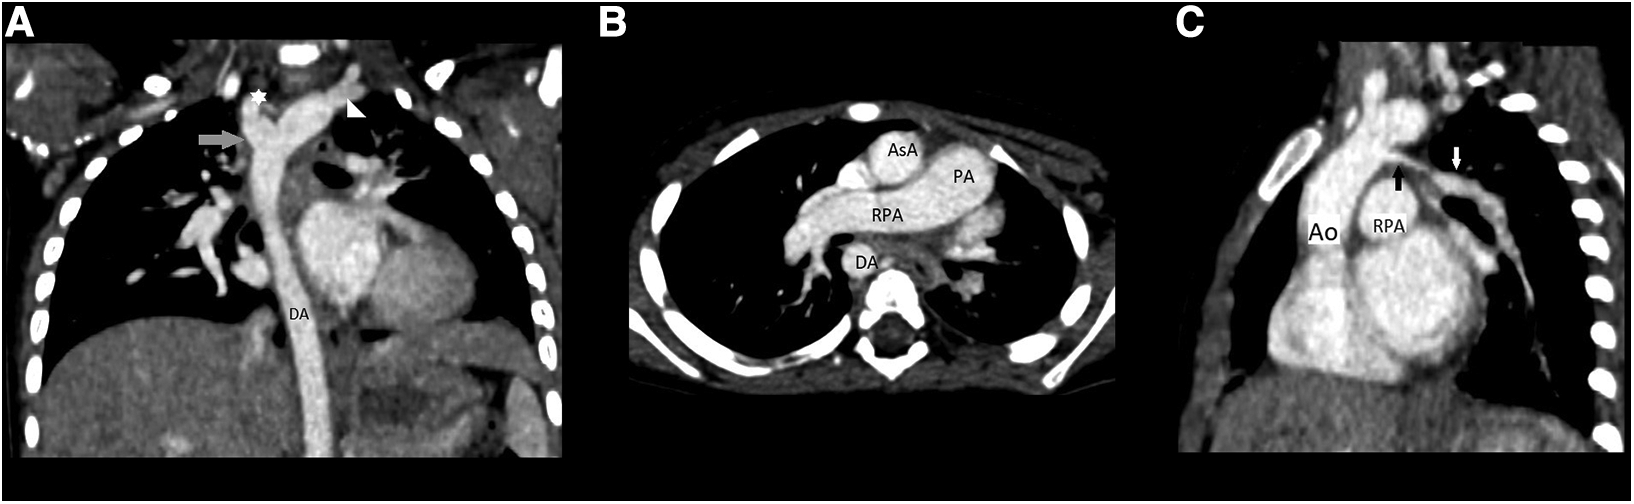

The patient was admitted to the pediatric department for further diagnostic approach. Wheezing persisted for two days and subsided without any specific treatment. A transthoracic echocardiogram revealed absence of the left pulmonary artery, and right arch of aorta and anomaly of subclavian arteries was suspected (Figure 2). No other congenital heart defects or signs of pulmonary hypertension were noted. The diagnosis was confirmed by computed tomography (CT) scans of the chest that demonstrated elongation of the aorta and an aberrant right subclavian artery with Kommerell's diverticulum (KD) (Figure 3A), as well as absence of the left pulmonary artery (Figure 3B), with a hypoplastic upper lobe of the left lung. Atypical vascular branches dividing from the aorta and forming the vasculature of the left lung were also visible (Figure 3C, Supplementary File S1). The mediastinum was slightly shifted to the left. We suspect that atypical vascular branches are aortopulmonary collaterals. Flow supply through ductus arteriosus to the atypical hilar segment of left pulmonary artery could be suspected as well but only angiography could specify the exact anatomy of those branches. We clarified that there is no compression to the airways of vasculature structures during bronchoscopy.

Figure 3. (A) Chest CT angiography scan, coronary reconstruction: elongation of the aorta and an aberrant right subclavian artery with KD; (B) chest CT angiography scan: absence of the left pulmonary artery; (C) chest CT angiography reconstruction: atypical vascular branches dividing from the aorta and forming the vasculature of the left lung; Abb.: Ao, aorta; AsA, ascending aorta; DA, descending aorta; PA, pulmonary artery; RPA, right pulmonary artery; star, abberant right subclavian; triangle, left subclavian artery; grey arrow, KD; black arrow, atypical branch; white arrow, anomalous left lung vascular bundle.

Heart and mediastinal displacement, ipsilateral elevation of the diaphragm, and contralateral hyperinflation are observed on chest radiographs in patients with isolated UPAA, whereas KD can only be diagnosed after chest CT or magnetic resonance imaging (MRI) (1, 3–6). Similar abnormalities of UPAA on chest radiography were observed in our patient. An abnormal x-ray scan led to a detailed examination. A transthoracic echocardiogram revealed the absence of the left pulmonary artery and was suspicious for malformations of the aortic arch vessels. Other researchers also reported cases of asymptomatic UPAA incidentally suspected after abnormal findings in the chest x-ray image (3, 4). A contrast-enhanced chest CT scan was sufficient to confirm the diagnosis of left UPAA, and it enabled us to detect an asymptomatic, extremely rare type of KD (1, 3, 4). Chest MRI or ventilation-perfusion scintigraphy can also be used to diagnose UPAA (1).